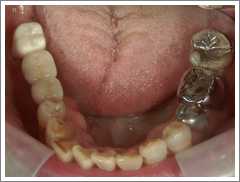

症例 8 むし歯によって失った下の奥歯に対してインプラント治療を行ったケース

治療前

むし歯が進行して右下の歯を2本抜かなければならなかった症例です。

入れ歯では違和感が強く使用できなかったため、インプラント治療を行いました。

インプラント治療によって奥でも咬むことができるようになり、違和感なく食事をすることができるようになりました。 ( 50代 男性 )